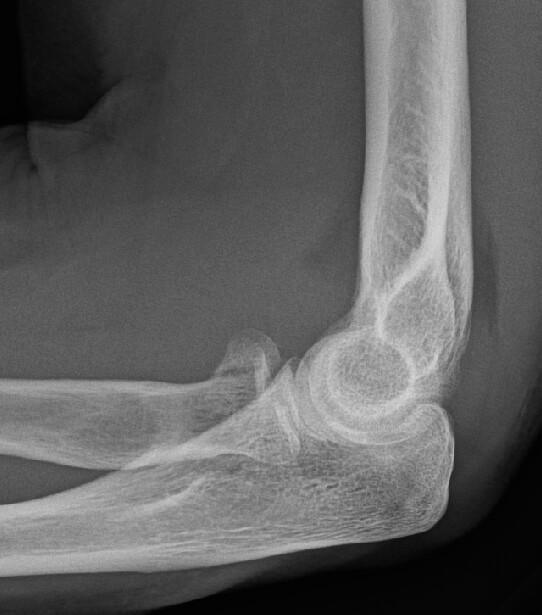

James Heilman, MD - Own work, CC BY-SA 4.0, Link

Non ou peu déplacée (I et II) : vérifier cliniquement s’il existe un blocage en prono-supination.

Si absence de blocage mécanique (même si douleur), traitement fonctionnel avec coude au corps 48 heures puis mobilisation libre. Consultation à J7.

« Equivalent » d’une fracture = signe de la voile. Traitement fonctionnel avec coude au corps 48 heures puis mobilisation libre. Consultation orthopédique à J7.

Déplacée ou avec blocage : avis chirurgical.